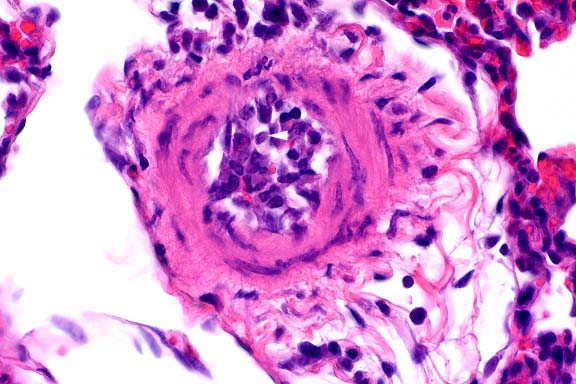

10x

obj

40x

- Case 16-3. Liver. Liver parenchyma is multifocally

necrotic and partially replaced by myriad Histomonas trophozoites,

10-20u in diameter, which are fragmented, pale, amphophilic,

and surrounded by narrow rims of clear space.

20x

- Case 16-3. Colon. The lamina propria is diffusely

expanded by macrophages, lymphocytes, heterophils, and fragmented,

pale, granular Histomonas amoeba. At points of mucosal erosion,

these inflammatory cells stream into the gut lumen.

AFIP Diagnoses:

- 1. Liver: Hepatitis, granulomatous, necrotizing, multifocal

to coalescing, moderate, with numerous protozoa, chicken, avian.

- 2. Cecum: Typhlitis, lymphoplasmacytic, histiocytic, and

heterophilic, diffuse, moderate, with protozoa and cecal core.

- Some microslides contain cross-sections of intraluminal cecal

nematodes.

- The classical macroscopic lesions of histomoniasis include

bilaterally enlarged, hemorrhagic ceca that have a thickened

mucosa and are filled by caseo-necrotic, yellow-green, laminated

material (cecal cores). The cecal mucosa may also be necrotic

and ulcerated. In the liver, there are multifocal to coalescing,

circular, depressed, greenish-yellow areas of necrosis that are

circumscribed by a thin raised ring of parenchyma. The hepatic

lesions have been described as target-like. Microscopically,

the histomonads can be identified within areas of inflammation

in the cecae and within necrotic areas of the liver on routine

hematoxylin and eosin stained sections. Visualization of the

protozoal trophozoites may be enhanced by the periodic acid-Schiff

reaction, especially in chronic lesions that contain few organisms.